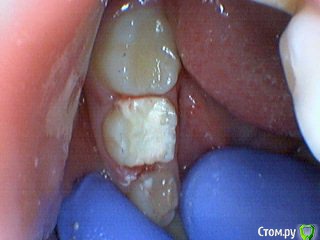

Давлетшин Опубликовано 29 декабря, 2017 Поделиться Опубликовано 29 декабря, 2017 (изменено) Друзья. Расскажите, не поменялось ли ваше отношение к пульпотеку и пр.Почему пломбы поверх пульпотеку такие ужасно жёлтые? Что сделать можно. Или что я делаю не так? "Друзья" так приятно перед новым годом. К пульпотеку не поменялось (устраивает вполне) , к пульподенту скептическое отношение, хоть и тоже работаю. Пломбы сразу желтые или через полгода - год- два? Очень тяжело что то советовать он лайн не видя как человек работает. В фото первая цифра пациент, вторая-третья номер зуба, четвертая порядок фото. Я после наложения пульпотека , стараюсь убрать излишки, или аккуратно на устья каналов накладываю, в пульповую камеру СИЦ, и сверху пломбу, Убрать излишки и со стенок, аккуратно в том числе и бором. В третьем клиническом случае, неудача. Зуб удалил сам же через 3 месяца. причину вижу в том что на рентгене не увидел (или так сделали снимок?) вертикальный тип рассасывания практически до бифуркации., может и потому что ребенок ОЧЕНЬ плохо сидел. За фото не пинайте сильно, не инстаграмм все таки,да и тяжело ребенка лечить и фотки делать. или наоборот пинайте может лучше начнем фоткать. P.s. Добавлю протокол как лечу с пульпотеком, хр.фибр.пульпит1. анестезия2. кофер ( если дает)3. раскрытие кариозной и пульповой камеры4. удаление коронковой пульпы маленьким эскаватором, я стараюсь "отрубать" пульпу5. остановка кровотечения сухим ватным шариком, 0,5-1-2 минуты6. пульпотек на устья7 СИЦ в пульповую камеру8 со стенок остатки пульпотека соскребаю бором фиссурным , цилиндрическим, там же фальц9. Пломба. может что то и зыбыл ну и оценка только позитивная перед НГ Изменено 29 декабря, 2017 пользователем Давлетшин 2 Ссылка на комментарий